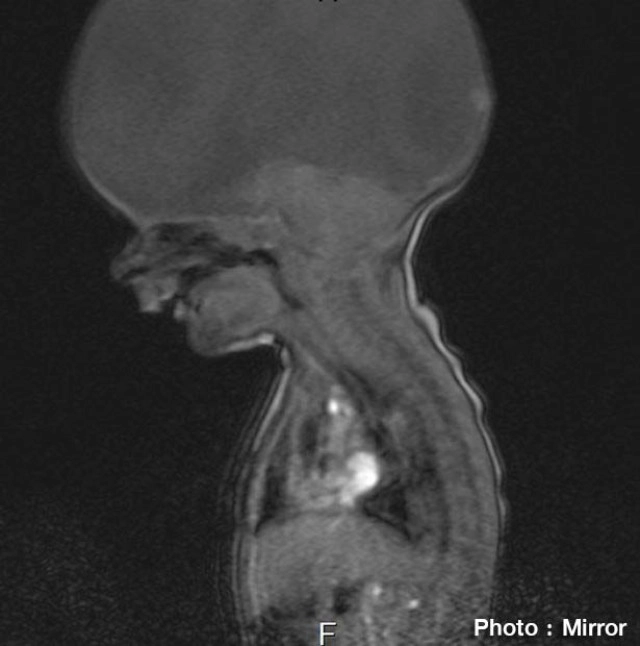

โดย แพทย์ระบุว่า แอรอน มีความผิดปกติของร่างกายมาตั้งแต่เกิด อาจมีชีวิตอยู่ได้ไม่นาน เมื่อสมองของเขาได้หายไป เหลือเพียงก้านสมอง ที่ยังคงช่วยให้อวัยวะภายในบางส่วนยังคงทำงานได้ สามารถหายใจ มองเห็นและได้ยินเสียง ถือเป็นสภาวะสุขภาพที่หาได้ในเด็กทารกเพียงสองในหนึ่งหมื่นของเด็กทารกที่จะเกิด เรียกว่า โรค"โฮโลโปรเซนเซฟาลี" เป็นความผิดปกติของศีรษะและสมอง ส่วนมากเด็กจะเสียชีวิตในท้องก่อนที่จะคลอดออกมา หรือมีชีวิตอยู่ได้ไม่นาน